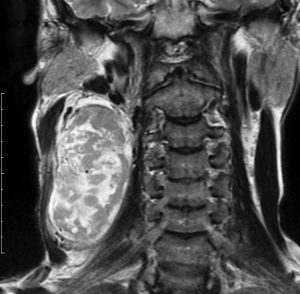

左は1991年,右は2006年のMRI画像です。15年間で腫瘍のサイズは変わっていません。

1991年に50代の女性にみつかったものでした。黄色に示したルートで摘出できないわけではありませんが,右後頭部が腫れてきたという訴えとホルネル症候,軟口蓋麻痺しかなかったので,何も治療しないでほっておきました。2016年まで25年間観察し続けました。症状の悪化は全くなく元気に暮らしておられます。グロームス腫瘍はある一定の年齢になると増大しないという性質を持っている良性腫瘍です。これを大々的な頭蓋底外科手術で摘出するするという愚を犯してはなりません。